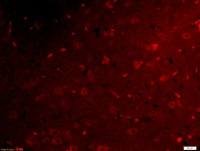

| 产品图片 | ![]() Sample: MDCK(Dog) Cell Lysate at 40 ug Primary: Anti-Nephrin (bs-10233R) at 1/500 dilution Secondary: IRDye800CW Goat Anti-Rabbit IgG at 1/20000 dilution Predicted band size: 138 kD Observed band size: 138 kD ![]() Sample: Liver (Mouse) Lysate at 40 ug Primary: Anti-Nephrin (bs-10233R) at 1/300 dilution Secondary: IRDye800CW Goat Anti-Rabbit IgG at 1/20000 dilution Predicted band size: 138 kD Observed band size: 138 kD ![]() Tissue/cell: mouse kidney tissue; 4% Paraformaldehyde-fixed and paraffin-embedded; Antigen retrieval: citrate buffer ( 0.01M, pH 6.0 ), Boiling bathing for 15min; Block endogenous peroxidase by 3% Hydrogen peroxide for 30min; Blocking buffer (normal goat serum,C-0005) at 37℃ for 20 min; Incubation: Anti-Nephrin Polyclonal Antibody, Unconjugated(bs-10233R) 1:200, overnight at 4°C, followed by conjugation to the secondary antibody(SP-0023) and DAB(C-0010) staining ![]() Tissue/cell: rat kidney tissue; 4% Paraformaldehyde-fixed and paraffin-embedded; Antigen retrieval: citrate buffer ( 0.01M, pH 6.0 ), Boiling bathing for 15min; Block endogenous peroxidase by 3% Hydrogen peroxide for 30min; Blocking buffer (normal goat serum,C-0005) at 37℃ for 20 min; Incubation: Anti-Nephrin Polyclonal Antibody, Unconjugated(bs-10233R) 1:200, overnight at 4°C, followed by conjugation to the secondary antibody(SP-0023) and DAB(C-0010) staining ![]() Blank control: RSC96(blue), the cells were fixed with 2% paraformaldehyde (10 min) and then permeabilized with ice-cold 90% methanol for 30 min on ice. Isotype Control Antibody: Rabbit IgG(orange) ; Secondary Antibody: Goat anti-rabbit IgG-PE(white blue), Dilution: 1:200 in 1 X PBS containing 0.5% BSA ; Primary Antibody Dilution: 1μg in 100 μL1X PBS containing 0.5% BSA(green). ![]() the cells(293T) were fixed with 2% paraformaldehyde (10 min). Isotype Control Antibody: Rabbit IgG(orange) ; Secondary Antibody: Goat anti-rabbit IgG-PE(white blue), Dilution: 1:200 in 1 X PBS containing 0.5% BSA ; Primary Antibody Dilution: 1μg in 100 μL1X PBS containing 0.5% BSA(green). |